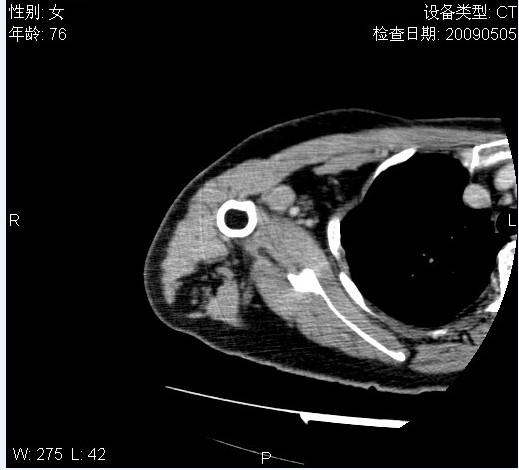

标题: CT19811:女,76岁,右上臂肿物1个月 [打印本页]

标题: CT19811:女,76岁,右上臂肿物1个月

使用了造影剂,可惜效果不太好

右肱骨上段软组织内见梭形低密度影,边界清楚,最长径约54mm.

病理结果:脂肪瘤。术中见肱骨骨膜受侵,有出血,量不详。

当时诊断意见:右肩三角肌内蔓状血管瘤(先天性动静脉瘘)。

本人对病理结果有个疑问:单纯的脂肪瘤内为什么有条状软组织影,那应该脂肪肉瘤才对啊?

该病例增强效果欠佳,由于经验欠缺,我们注射对比剂是由下肢足背静脉给药。注速2.0。虽然如此,但我们可以看到肿块内部条状软组织影是强化的,而且是连续的,并可见供血动脉是由腋动脉的其中一支即肩胛下动脉分出。从这些征象我们可以得出诊断:蔓状务血管瘤。

可病理偏偏为脂肪瘤,我怀疑取材有问题。因为蔓状血管瘤异常扩张的静脉外周是脂肪成分,它可以侵犯肌组织及骨骼。当取材于外周,那当然是脂肪瘤。此时我认为临床的最终诊断不应单从病理出发,应该综合考虑。